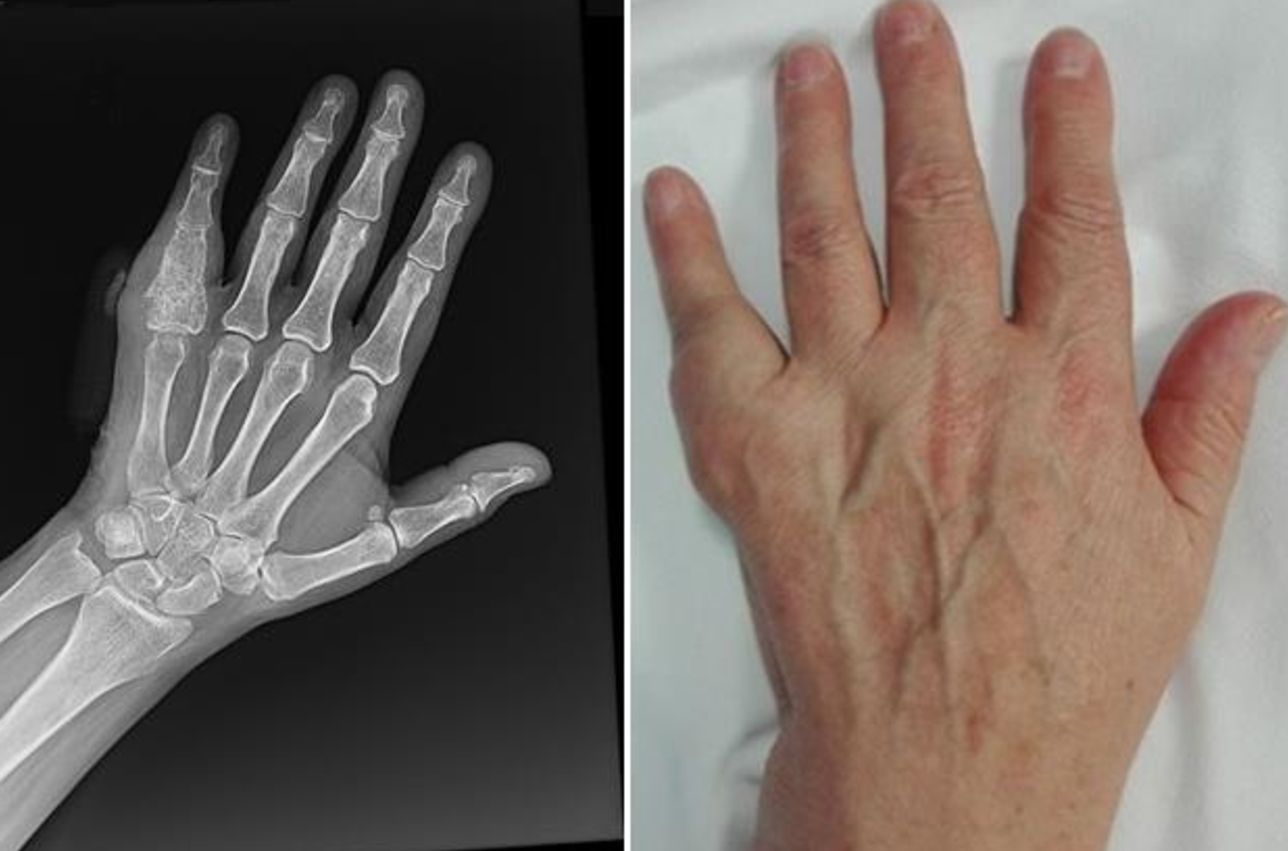

1、骨肉瘤的6个早期信号如下疼痛早期常表现为轻微间歇性疼痛,夜间或运动后加重,随病情进展逐渐加剧,影响日常活动和睡眠质量疼痛部位多位于长骨干骺端如股骨远端胫骨近端,需与生长痛或运动损伤区分肿块病变部位可触及质硬边界模...